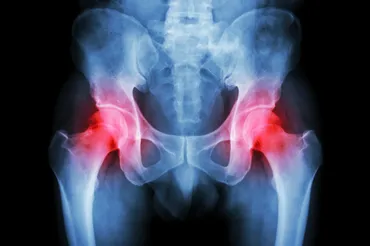

✅ 大腿骨頭壊死症は、30~60代で発症することが多く、ステロイド剤の大量服用やアルコール摂取も原因となり、進行すると歩行困難になる。

治療法としては、若い方には骨切り術が、高齢者や壊死範囲が大きい場合には人工関節置換術が選択されることが多いです。